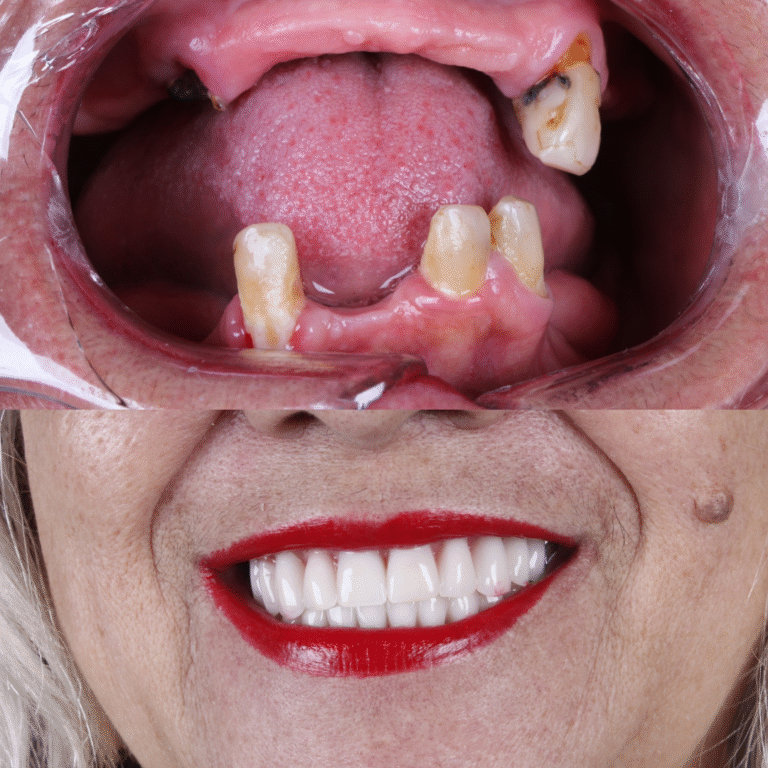

O All-on-Four é um protocolo de implantes dentários que utiliza apenas 4 implantes para fixar uma prótese total, substituindo todos os dentes da arcada.

Diferente de técnicas convencionais, não exige enxertos ósseos na maioria dos casos, tornando o tratamento mais rápido e confortável.

Perderam todos os dentes ou têm dentes comprometidos e desejam uma solução fixa e duradoura.

Em muitos casos, é possível instalar dentes fixos no mesmo dia da cirurgia. Isso significa que o paciente recupera a estética do sorriso e a função mastigatória muito mais rápido do que em técnicas convencionais.

Segundo o Dr. Arnaldo, pioneiro em Belém na técnica do All-on-Four, o tratamento com implantes, especialmente a prótese protocolo, vai muito além da cirurgia.